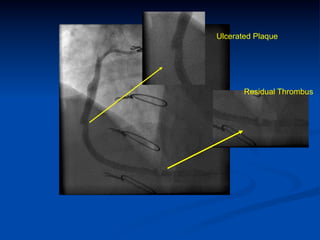

Ulcerated Plaque

Residual Thrombus

Ulcerated Plaque Residual Thrombus